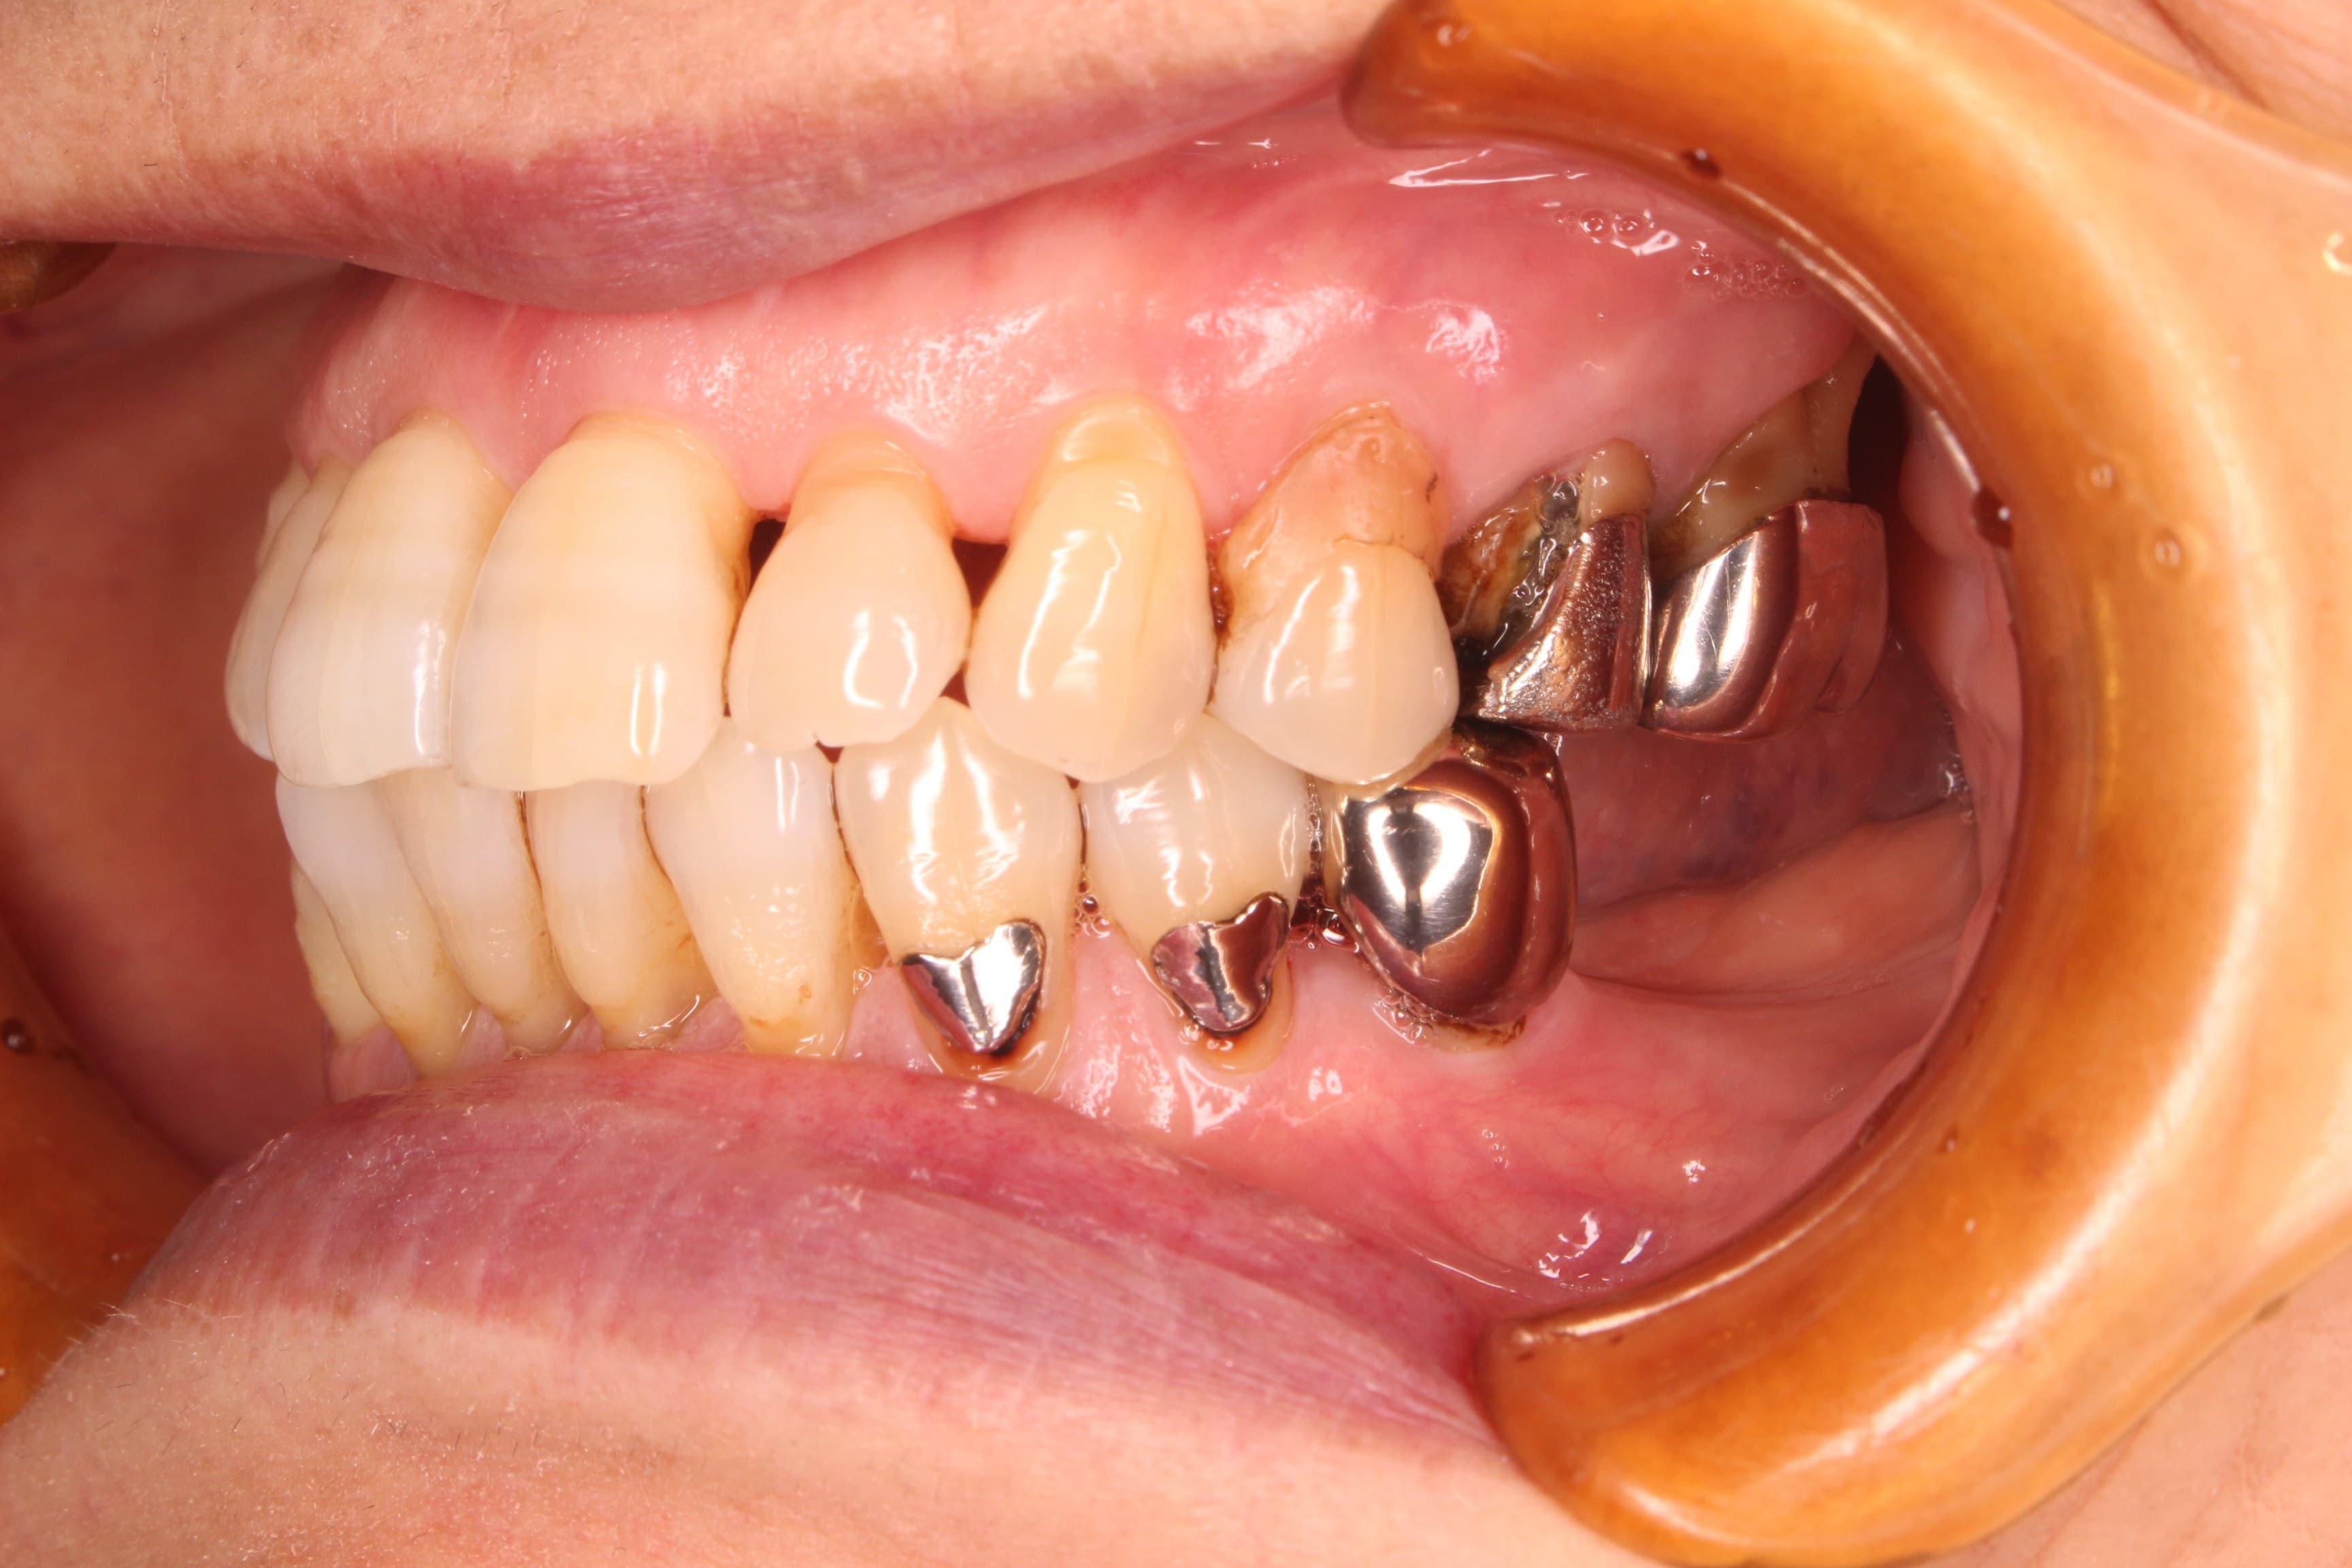

歯周治療終了後

※この後、折れた歯や虫歯、欠損部の治療を行っています。

幸いにも、まだ前歯部は多く残っており今から予防の為の治療をすれば、現状の維持が可能であることをお伝えして、歯周専門治療を行うこととなりました。

高齢ではありますが、初めてのブラッシングトレーニングも、しっかりとご自身のペースで取り組み、磨いて欲しい所をしっかりと磨けるようになりました。